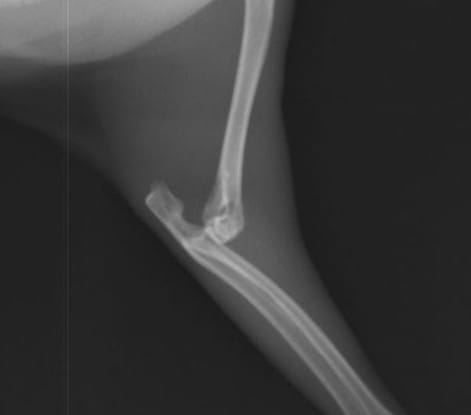

右前肢が動かなくなっており、レントゲン検査を行うと、

このように右前肢の肘関節が脱臼しています。